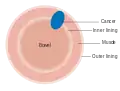

Dukes stage A bowel cancer; the cancer is only in the inner lining of the bowel. Dukes stage B bowel cancer; the cancer has invaded the muscle.

Dukes stage B bowel cancer; the cancer has invaded the muscle. Dukes stage C bowel cancer; the cancer has invaded the nearby lymph nodes.